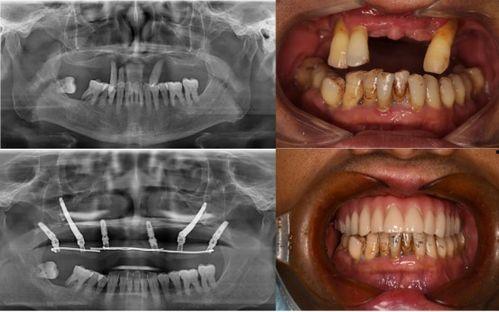

首先,让我们来回顾一下这个事件。据网友爆料,佛山某口腔医院在进行种植牙手术时,竟然出现了严重的医疗事故。视频中,一位患者在手术过程中突然大出血,医护人员却显得手忙脚乱,场面一度十分混乱。这个视频一经曝光,立刻引起了广大网友的关注和热议。

那么,这个医疗事故背后到底隐藏着什么真相呢?据知情人士透露,这家口腔医院在手术过程中存在诸多违规操作。首先,手术医生并未具备相应的资质,而是由一位实习医生主刀。其次,手术过程中使用的医疗器械也存在严重问题,比如消毒不彻底、过期等。这些因素共同导致了这场悲剧的发生。

面对这场突如其来的灾难,患者们的心情无疑是悲痛的。他们纷纷表示,自己原本希望通过种植牙手术重拾自信,却没想到遭遇了这样的噩梦。为了维权,患者们开始四处奔波,寻求法律援助。维权之路并非一帆风顺,他们面临着诸多困难。